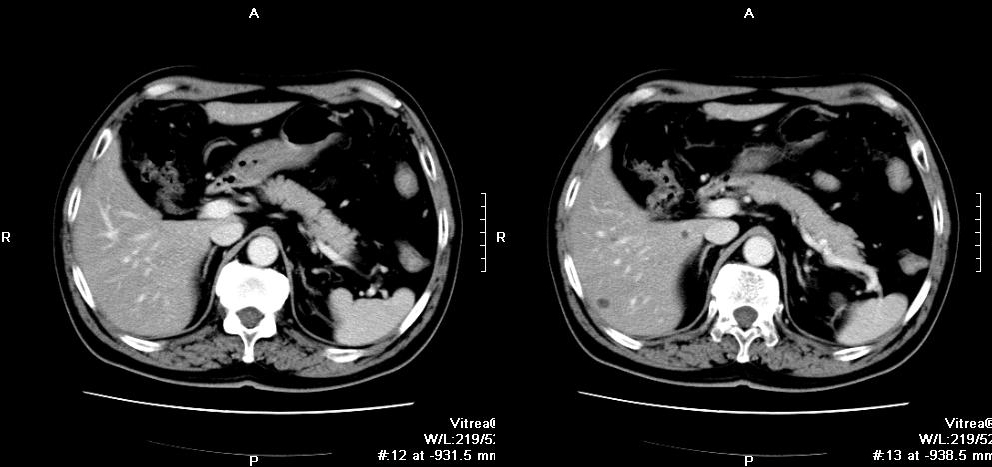

3.CT掃描:對(duì)診斷腎上腺囊腫有重要價(jià)值,可明確腫塊為囊性還是實(shí)質(zhì)性,可查出5mm以上的腫塊。腎上腺真性囊腫為圓形或橢圓形,邊緣光滑,密度與水相仿.CT值為0~20Hu,周圍繞以密度較高的薄壁,約有15%的上皮性囊腫可出現(xiàn)殼樣鈣化改變。假性囊腫囊壁較厚,出血或感染時(shí)囊腫密度不均,CT值增高。寄生蟲(chóng)囊腫表現(xiàn)為囊腔內(nèi)有分隔改變。